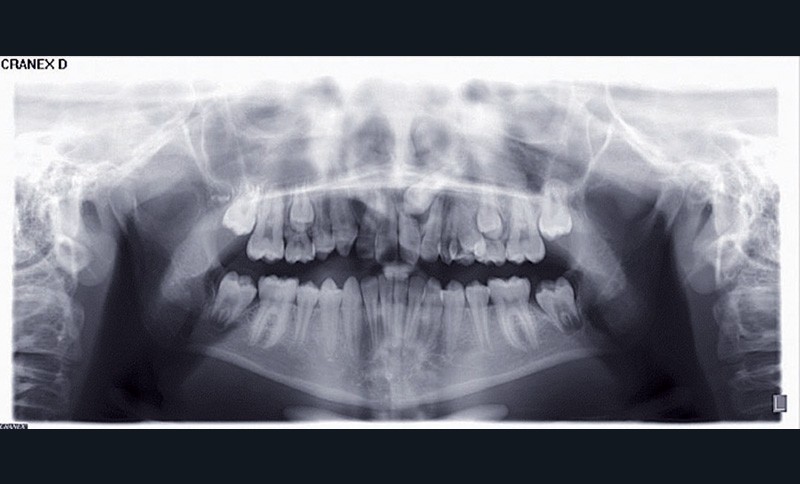

Rappel de la problématique. Mademoiselle O. âgée de 13 ans en classe I squelettique mésodivergente présente la persistance de 63. La panoramique et l’examen tomodensitométrique montrent une transposition de la 23 qui évolue au-dessus de la 21 et a entraîné une résorption radiculaire de celle-ci.

D’après les documents fournis, il s’agit d’une transposition de 23, transposition partielle, l’apex étant en bonne position (fig. 1).

Il n’y a aucune autre image suspecte de la denture, pas d’anomalie de développement des dents, tout juste des apex plutôt fins. La racine de 22 est intacte, les autres dents visibles sur le document ne montrent pas de résorption apicale. La 63 est intacte avec une longue racine non résorbée.